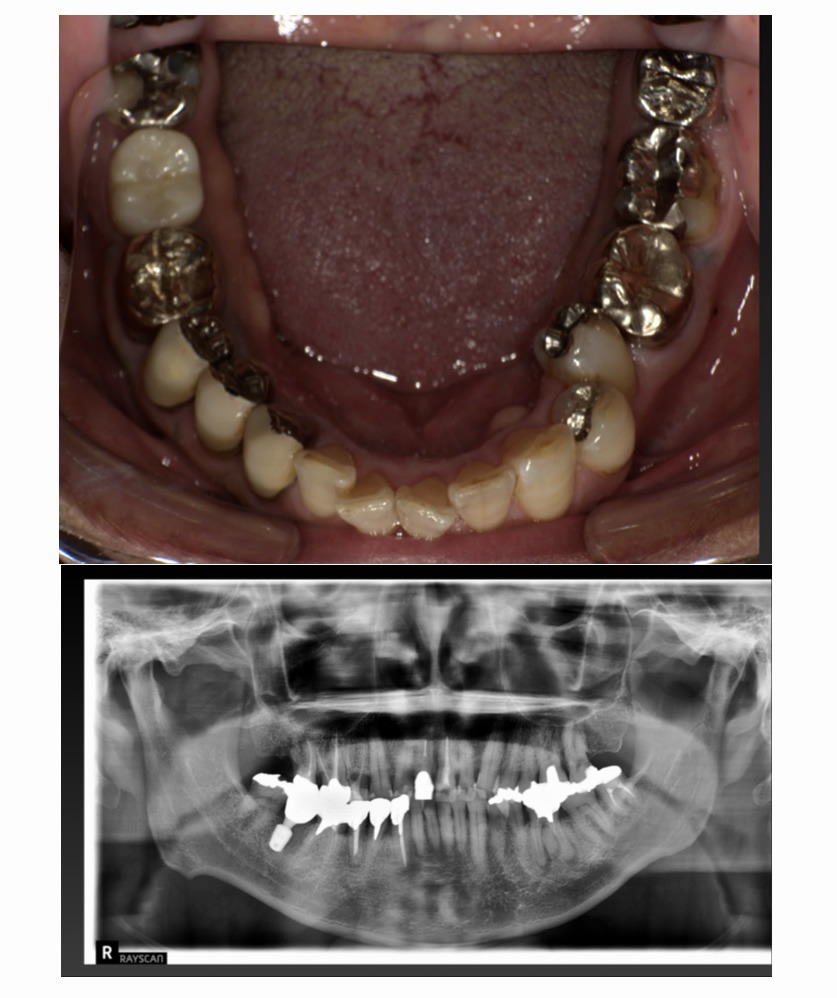

症例1

Before

After

年齢/性別 | 60代/女性 |

|---|---|

主訴 | 咬むと痛いのでインプラントにしたい |

治療内容 | 歯が割れていて咬むと痛いのでインプラント希望 |

治療期間 | 3ヶ月 |

費用 | 518,100円(税込み) |

副作用/リスク | 術後に多少の痛みや腫れが出ることがある。歯肉退縮がおきると、歯と歯肉の間に隙間が生じることがあります。 |